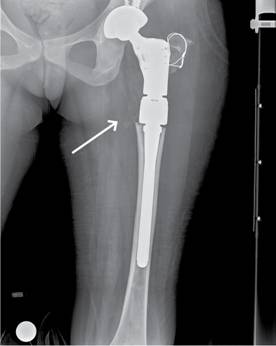

Femenino de 30 años de edad con fractura de cadera izquierda a los 15 años de edad no asociada a evento traumático, el manejo fue conservador y la paciente presentó discrepancia en la longitud de ambas extremidades inferiores por acortamiento del lado afectado. A los 29 años de edad, la paciente se embaraza, durante este tiempo el acortamiento de la extremidad afectada aumentó 5 cm. La radiografía de pelvis mostró deformidad radio-opaca en cabeza femoral izquierda en «cayado de pastor» (Figura 1), datos confirmados por tomografía axial computarizada (Figura 2), por lo que se solicitó valoración por endocrinología manejándola con bifosfonatos y su embarazo concluyó adecuadamente. En el puerperio mediato sufrió caída desde su plano de sustentación, contusión directa en cadera izquierda, dolor, incremento de la deformidad, crepitación ósea y la radiografía simple mostró la deformidad ya mencionada con una fractura subtrocantérica en sitio de displasia, imagen de vidrio despulido, de apariencia quística en cuello femoral, zona trocantérica y subtrocantérica (Figura 3). Ante estos hallazgos se le realizó resección del sitio de lesión y colocación del Sistema Modular de Revisión Femoral ArcosMR (Figura 4). A los 10 meses de la operación la evolución de la paciente era satisfactoria (Figura 5).

Figura 3: Fractura subtroncantérica en sitio de displasia de fémur proximal, deformidad en varo en el sitio de lesión.